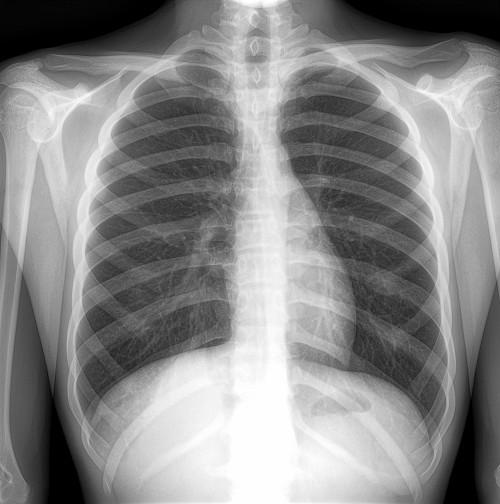

(动态DR 17*17大幅面图像)

对比目前市场上的众多DR品种,在精准发现以及精准诊断上动态DR是目前技术最为先进的。动态DR配备的是17*17寸的大幅面探测器,纵横面积可以达到43*43CM,一个幅面就可以清晰的看清整个胸部或者腹部,配合900多万的图像像素,在筛查的过程中可以通过动态透视观察,点片的时候只需要动静切换即可,受检者呼吸运动时不会产生运动伪影,影像的一致性、对比性、均衡性与细腻度都表现优异。造影过程中可以进行造影视频的动态保存和回放,对于基层乡镇医院来说,是一款非常贴合实际需求的DR设备。